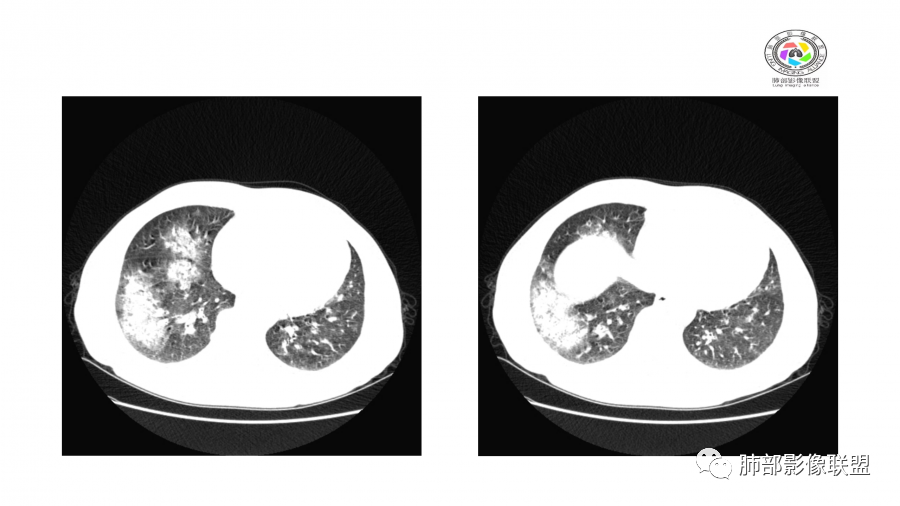

中年男性,高血压,肾功能衰竭,贫血病史,尿潜血阳性。3.8双肺野多发斑片磨玻璃实变影,结节影,边缘模糊,周围有晕征,内见支气管充气征,主要沿支气管血管束分布,部分胸膜下分布,3.12号病灶有吸收好转,4.8号斑片实变影基本吸收,主要沿支气管血管束分布结节影,边缘平直收缩,4.28病灶大部分吸收好转,双肺支气管血管束增粗,有少量结节影。考虑ANCA相关性血管炎可能性大,第一次片子觉得隐球菌不排除,但是后面没有抗真菌治疗就吸收了,觉得隐球菌可能性不大。

影像:双肺散在实变影及毛玻璃影,实性病变周围可见晕征,病灶于肺外围区域优势分布,病变区引流支气管未见增厚,考虑血管相关病变;3月、4月复查CT提示肺内病灶呈游走性,此起彼伏。

病灶此起彼伏

10天后:病灶继续吸收好转